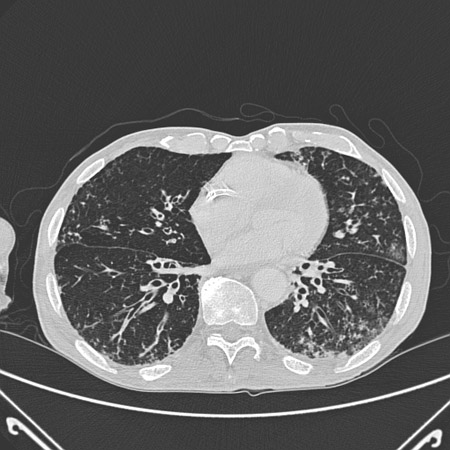

Bronquiectasia

Tomografia computadorizada do tórax com vias aéreas dilatadas e espessadas e um padrão de árvore em brotamento

Dos arquivos do Dr. Sangeeta M. Bhorade; uso autorizado